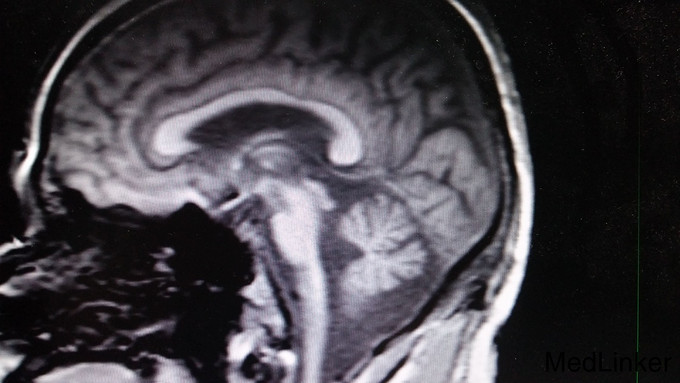

患者,男,62岁,患者因“行走不稳10年余,渐进性加重伴言语不清2年余”入院。10余年前无明显诱因下出现行走不稳,与当地医院就诊,行颅脑磁共振提示小脑萎缩,随后间断服药治疗,行走不稳未见改善,并逐渐加重,双上肢持物不稳,2年余前开始出现言语不清,行走及站立时双下肢乏力、不稳,进食可出现呛咳,于湖南湘潭医院拟“小脑性共济失调”治疗,治疗效果不明显,今患者进一步诊治。否认家族中类似病史。

构音欠清,双眼外展活动受限、悬雍垂左偏,左侧咽反射减弱,双下肢肌力4级,共济失调。辅查: 1. 头颅MRI:小脑萎缩,桥脑、延髓体积偏小,注意变性疾病(橄榄桥脑小脑萎缩)可能; 2. 肌电图:神经性损伤;诱发电位:双上下肢体和双侧视觉异常体感诱发电位。